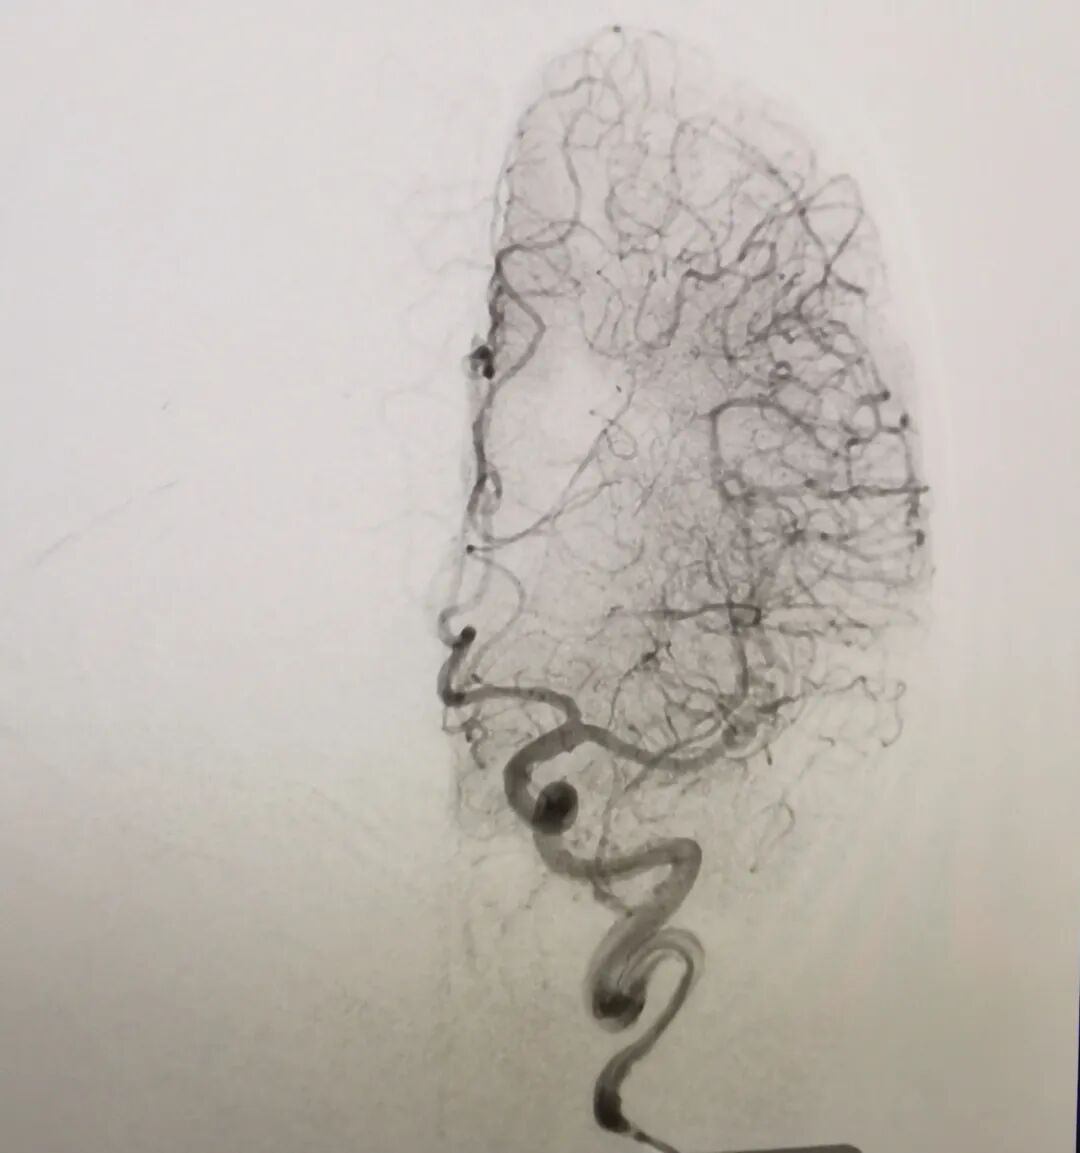

关键时刻,卒中中心团队快速评估:余大伯虽然无法溶栓,但其发病时间短、大血管闭塞明确,且经CTP评估存在可挽救的“缺血半暗带”(即未完全坏死的脑组织),符合动脉取栓条件。经过与家属沟通,余大伯被火速转运至导管室。两小时后,血栓成功取出,血管再通;次日,他奇迹般苏醒,左侧肢体可抬,语言功能恢复,思维清晰。经后期规范治疗,余大伯出院时康复良好。这场与时间的赛跑,因动脉取栓技术的及时介入,画上了圆满的句号。

闭塞动脉成功开通

动脉取栓技术是脑卒中救治的“最后一道防线”。它是通过微创介入手段,将取栓支架或抽吸导管送入堵塞的脑血管,直接“抓捕”或“抽吸”血栓,快速开通闭塞血管,恢复脑部血流。与传统药物溶栓相比,它能更直接、高效地解决大血管堵塞问题。